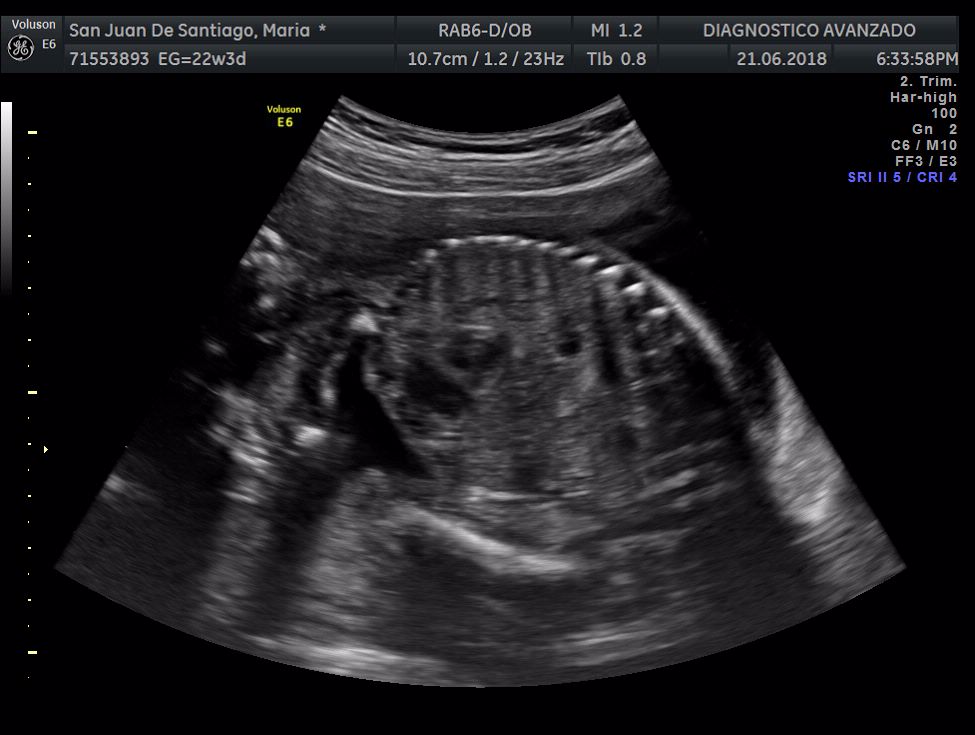

¡Hola a todos! Hoy hemos ido a hacer la tradicional ecografía 3D de la niña, os dejamos todo el material (aunque es un poco demasiado).